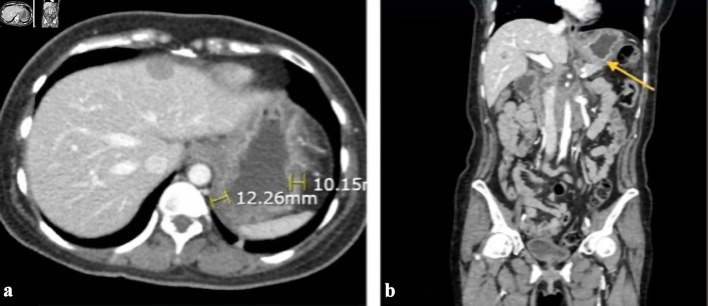

Hepatoid adenocarcinoma of the stomach (HAS) is a rare type of gastric cancer with unique clinicopathological features. HAS has a poor prognosis because of early liver, lung, and lymph node metastasis. Owing to its rarity and malignant potential, data on its pathophysiology and management are scarce. Herein, we describe a case of alpha-fetoprotein-producing HAS (AFP-HAS) with metastases to the liver, lungs, and spine. The patient presented with a 3-month history of epigastric pain and intractable emesis, initially thought to be gastroparesis given her uncontrolled diabetes mellitus. Contrast-enhanced computerized tomography (CECT) of the abdomen and pelvis revealed thickening of the gastric wall with hepatic metastases. Upper endoscopy revealed a fungating gastric mass, and the histopathology confirmed AFP-HAS. The patient did not tolerate palliative chemotherapy and died 6 months after her gastric cancer diagnosis.